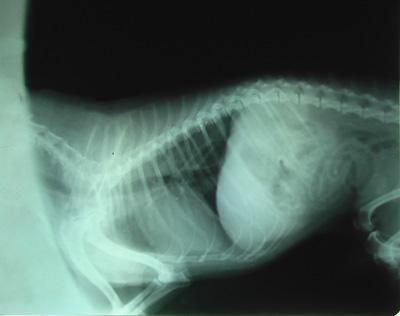

猫咪肺炎的检查方法

一般给猫咪做胸部X光检查和血常规来确定猫咪是否肺炎。也可通过超声波来检测肺部的感染。

▲感染肺炎的x光